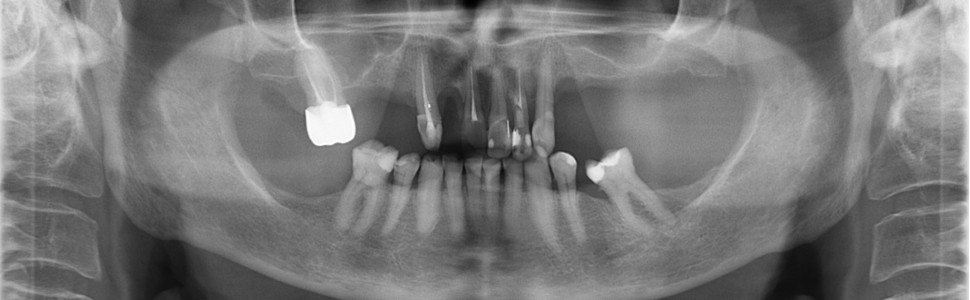

W artykule opisano przypadek ponownego leczenia endodontycznego zęba 22, w którym odnaleziono nieopracowany kanał dodatkowy. Po dokładnym rozpoznaniu i odkryciu prawdopodobnej przyczyny niepowodzenia pierwotnego leczenia przeprowadzono ponowne leczenie endodontyczne, z następującą szczelną odbudową zachowawczą. Po zakończonym leczeniu pacjentka nie skarżyła się na dolegliwości bólowe, a leczony ząb odzyskał pełną funkcjonalność.

The article describes the case of endodontic re-treatment of tooth number 22, in which an additional root canal has been found. After a thorough diagnosis and discovering a probable cause of previous treatment's failure, a re-treatment has been carried out with restorative filling. After the treatment, Patient has not been suffering from any pain and the tooth has regained its function.